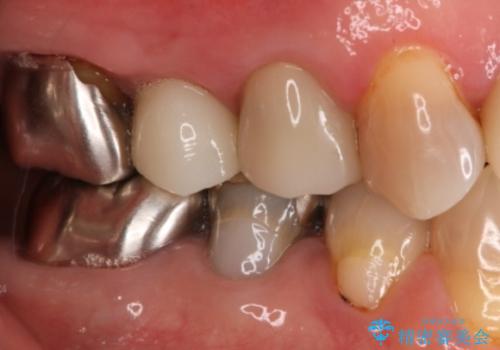

- 右上小臼歯の破折を理由に来院された患者様です。

残根状態で保存不可能と判断し、抜歯した上で補綴することを提案しました。

インプラント治療を希望されたので治療の期間・回数の少ない抜歯即時埋入インプラントでの治療を計画しました。

抜歯と同時にインプラントを埋入することで治療の期間・回数を減らし、患者様への負担を大幅に軽減することができます。

今回の患者様においては、術後に痛みは発生せず良好な経過を得ることが出来ました。